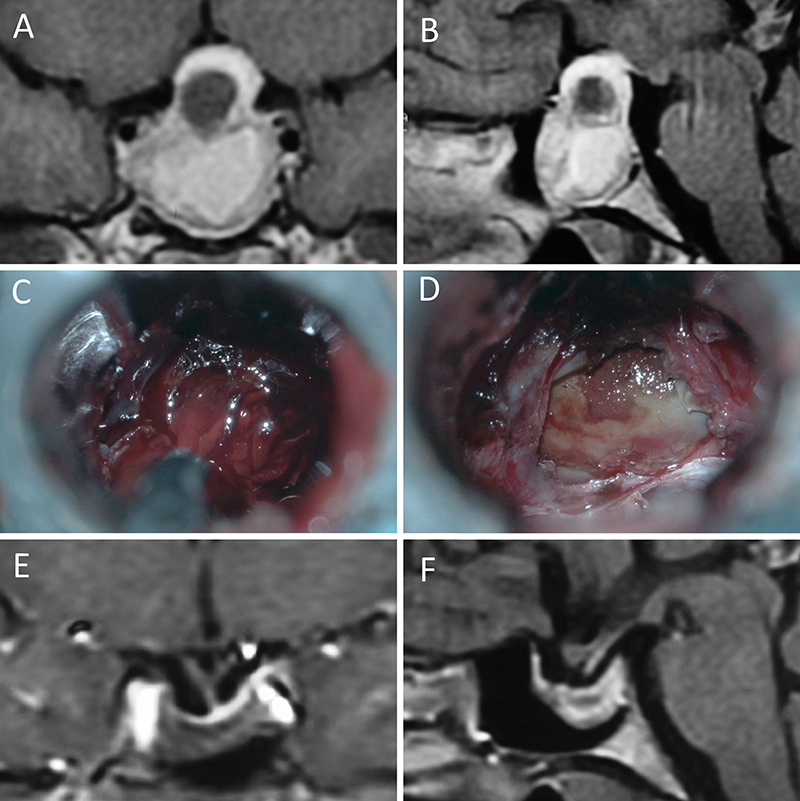

Figura 3: Macroadenoma no funcionante en un hombre de 64 años. El paciente presentó en el preoperatorio déficit visual que mejoró tras la cirugía. A-B: RM preoperatoria; C-D: intraoperatorio; E-F: RM postoperatoria.

Figura 4: Macroadenoma no funcionante en mujer de 32 años. La paciente presentó en el preoperatorio déficit visual que mejoró tras la cirugía. A-B: RM preoperatoria; C-D: intraoperatorio; E-F: RM postoperatoria.

Figura 5: Apoplejía hipofisaria hemorrágica en un hombre de 32 años. El paciente presentó cefalea y parálisis completa del III par. Tuvo restitutio ad integrum en el seguimiento. A-B: RM preoperatoria; C-D: intraoperatorio; E-F: RM postoperatoria.